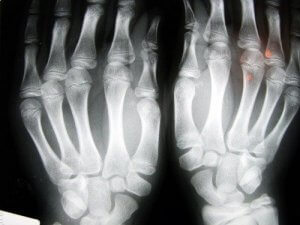

骨粗しょう症ってなに?

骨粗しょう症とは、骨密度が減少する病気です。骨に小さな穴が開き始めます。骨の内部組織のサイズが大きくなることで、さらにもろく、簡単に壊れやすくなります。

この病気は静かに進行し、骨にダメージが起きて初めてその状態に気づきます。

特に折れやすいのは手首の骨と、腰の脊椎です。腰回りの骨折は特に深刻で、即座に手術しなければ、後遺症が残る可能性があります。